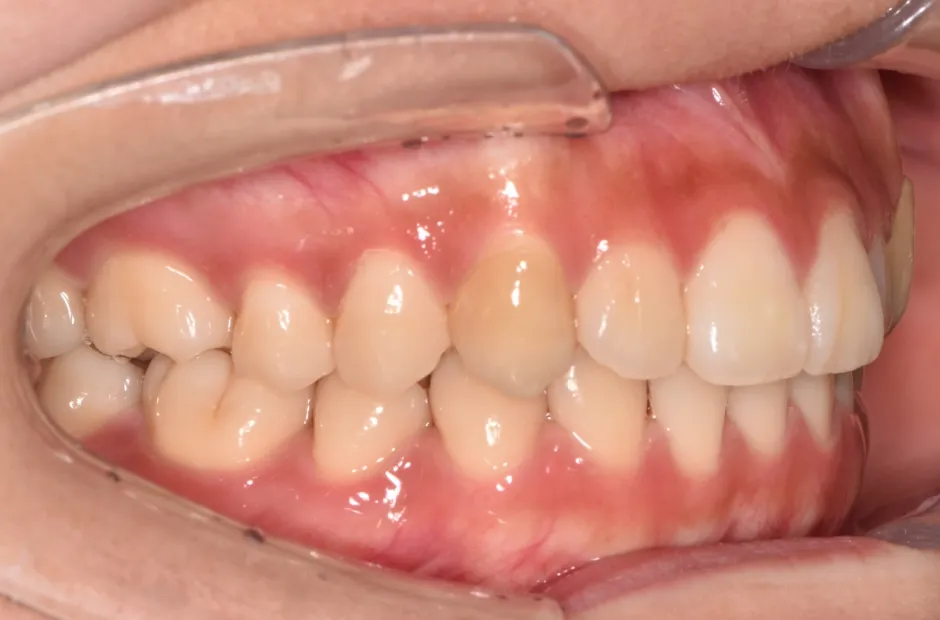

叢生

| 診断名・主訴 | 叢生 |

|---|---|

| 年齢・性別 | 43歳・女性 |

| 治療期間・回数 | 2年7か月 27回 |

| 治療に用いた主な装置 | 舌側矯正 |

| 抜歯部位 | 両顎4,4 |

| 治療費 | 100万円(税抜) |

| リスク・副作用 | 装置による違和感・疼痛・歯肉退縮・歯根吸収・虫歯のリスクなど |

治療前